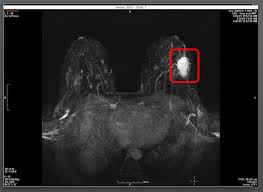

Aggressive Or Slow Growing Tumor Contrast Agent Gives Clues Healthcare In Europe Com from healthcare-in-europe.com You may notice dimpling or pitting, and the skin on your breast. (1) gary ulaner, md, phd, facnm. A rash isn't the only visual symptom of inflammatory breast cancer. Embedded video for what does cancer look like? Some benign conditions such as fibrocystic disease can look like cancer. Four of eight patients in whom a loss of fatty hilum was seen in an axillary node on mri were found to have cancerous lymph nodes at the time of their breast surgery. Tumor size is an important factor in breast cancer staging, and it can affect a person's treatment options and outlook. On the flip side, there are benign (not cancerous) breast changes which can mimic breast cancer as well.

Any area that does not look like normal tissue is a possible cause for concern.

The Radiology Assistant Mri Of The Breast from radiologyassistant.nl Your doctor may recommend a breast mri for the following: A breast mri captures multiple images of your breast. This is why we ask questions about menstrual cycle and hormone therapies prior to your study. What does breast cancer look like on a mammogram? Dcis on mri may create an area of irregular enhancement of the mri dye into the breast. The features of a malignant breast condition on mri scan are often to do with the outer irregular borders of a lesion. An mri can be used to look for a disease, such as breast cancer. If you are at risk of getting a certain disease, your caregiver may want to do an mri to look for signs of the disease.

An mri can help find a disease of the lungs or show tumors (growths) in the chest. But not every woman who has been diagnosed with breast cancer needs a breast mri. The features of a malignant breast condition on mri scan are often to do with the outer irregular borders of a lesion. A rash isn't the only visual symptom of inflammatory breast cancer. Any area that does not look like normal tissue is a possible cause for concern. A breast mri scan might also be used to assess the size of the cancer to check which kind of surgery is possible. They work to destroy the tumor or slow down the growth of cancer cells. This appears most commonly as streaking, known as linear enhancement. On the flip side, there are benign (not cancerous) breast changes which can mimic breast cancer as well. This means that the test finds a mass or other change that seems to show cancer but it is not cancer. Breast mri images are combined, using a computer, to create detailed pictures. What does breast cancer look like on a mammogram? The dye collection in the breast can also look clumpy or appear in a section of the breast, depending on the involvement of dcis.